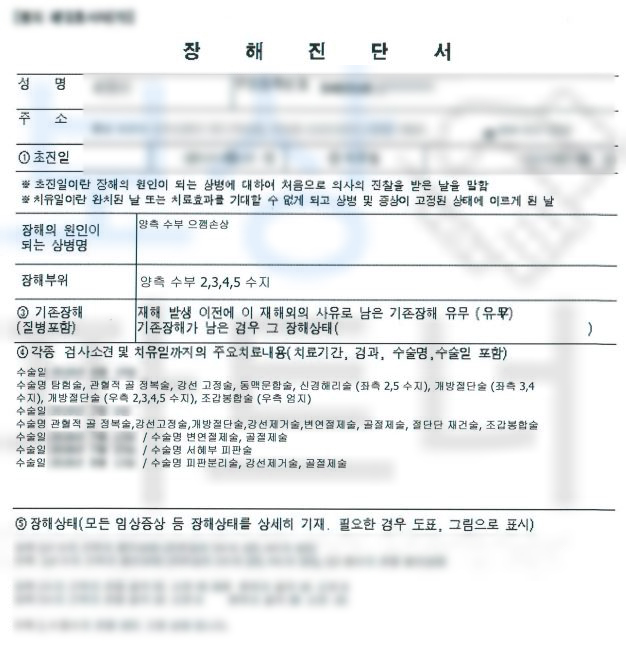

강@@님은 재해 당시 잔업 근무를 하던 날, 프레스 장비를 사용하던 중에 기계 오작동으로 인해 손가락이 으깨지는.. 사고를 당하셨습니다. 손가락의 상태는 심각했고 응급실 내원하여 수술을 받게 되었는데요, 수술을 실시하였음에도 손가락 으깸손상 s678 진단받아

강@@님은 손가락 일부가 절단될 수밖에 없었습니다. 산업 재해 근로자를 보호하기 위한 산재 보험을 통해 보상받을 수 있습니다.

**산재장해등급 5급 **인정받아

장해급여 연금으로 12,108,048원

지급받을 수 있었습니다. 산재장해등급은 다치고 수술했다고 해서 무조건 해당되는 것이 아닌 산재 장해판정 기준에 부합해야 지급되는 보험급여입니다. 강@@님의 상황을 보면 으깸손상 (압궤손상) s678 진단받아 무조건적으로 해당되어 보였지만

보상 파트너는 강@@님의 요양 기간 동안 의뢰인의 장해의 정도를 검토하고 미리 서류를 준비하였습니다. 요양 종결 시점 산재 장해급여 청구 시 종경 병원의 주치의와 함께 면담을 진행하여 객관적이면서 정확하게 장해판정이 이루어지도록 이끌었고 관할 공단의 장해판정까지 함께 주의 깊이 진행한 결과

산재 장해등급 5급